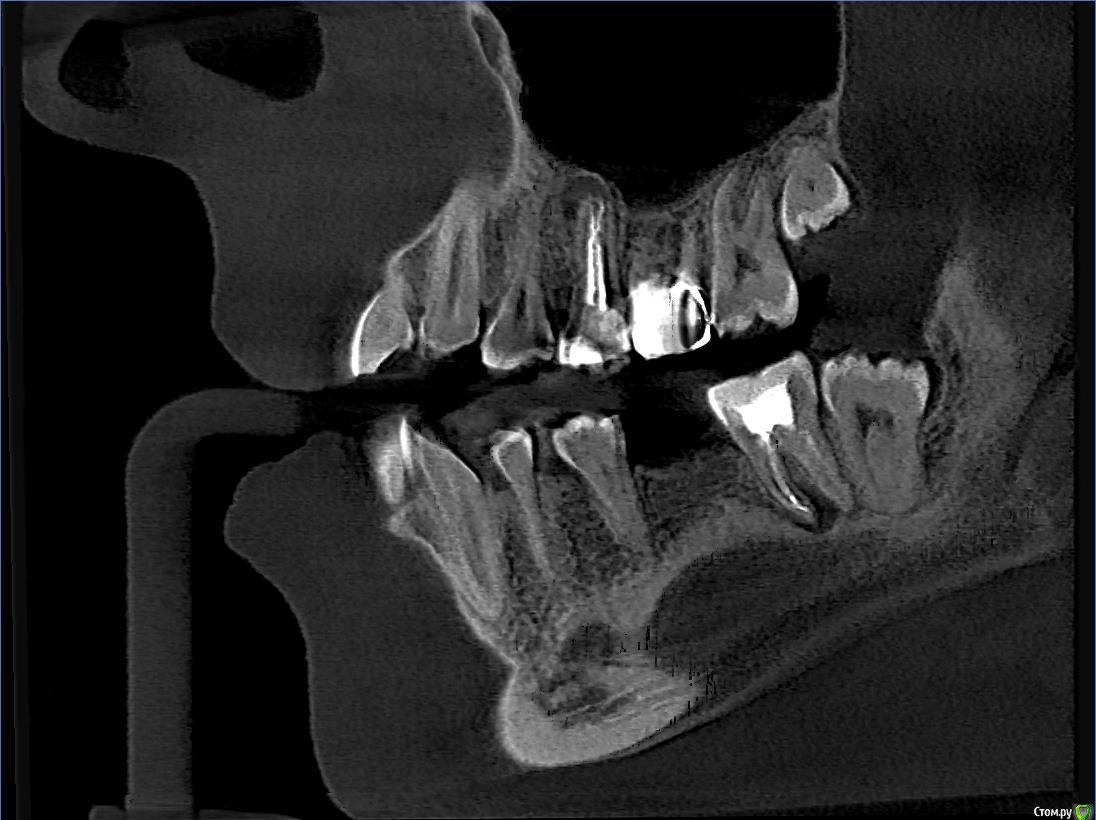

Wolfenstein Опубликовано 12 февраля, 2017 Автор Поделиться Опубликовано 12 февраля, 2017 Снимки прикрепил Ссылка на комментарий

Wolfenstein Опубликовано 12 февраля, 2017 Автор Поделиться Опубликовано 12 февраля, 2017 (изменено) вот еще один снимок Изменено 12 февраля, 2017 пользователем Wolfenstein Ссылка на комментарий

Wolfenstein Опубликовано 13 февраля, 2017 Автор Поделиться Опубликовано 13 февраля, 2017 Теперь вопрос, что стоит удалить? а что оставить? Ссылка на комментарий

Wolfenstein Опубликовано 13 февраля, 2017 Автор Поделиться Опубликовано 13 февраля, 2017 36 Ссылка на комментарий

red_butler Опубликовано 13 февраля, 2017 Поделиться Опубликовано 13 февраля, 2017 363.6 отсутствует, планируйте имплантацию и протезирование Ссылка на комментарий

Wolfenstein Опубликовано 13 февраля, 2017 Автор Поделиться Опубликовано 13 февраля, 2017 3.7 с пломбой Ссылка на комментарий

red_butler Опубликовано 14 февраля, 2017 Поделиться Опубликовано 14 февраля, 2017 что с ним?Да что же из вас жалобы клещами вытягивать приходится...с зубом - периодонтит, требуется повторное эндо лечение и последующее протезирование. Ссылка на комментарий

Wolfenstein Опубликовано 14 февраля, 2017 Автор Поделиться Опубликовано 14 февраля, 2017 Мне сказали, зуб с кистой и требуется удаление, но зуб вроде хороший, и хочется сохранить, думаю возможно ли это? Ссылка на комментарий

Паращук Роман Опубликовано 14 февраля, 2017 Поделиться Опубликовано 14 февраля, 2017 Найдите врача,что понимает толк в "лечении каналов" и с большей вероятностью вас ждет успех. Ссылка на комментарий

red_butler Опубликовано 14 февраля, 2017 Поделиться Опубликовано 14 февраля, 2017 Мне сказали, зуб с кистой и требуется удаление, но зуб вроде хороший, и хочется сохранить, думаю возможно ли это? Удалить успеете, ищите врача и перелечивайте. Ссылка на комментарий

DmitrySH Опубликовано 16 февраля, 2017 Поделиться Опубликовано 16 февраля, 2017 Ну и 24 кариес лечить, 25 ревизия каналов, 26 непонятно что с ним Ссылка на комментарий

Wolfenstein Опубликовано 28 февраля, 2017 Автор Поделиться Опубликовано 28 февраля, 2017 26 - удалил, это вкладка, 27 - нормальный , 28 - нет, он спрятался за деснами, там пусто Ссылка на комментарий